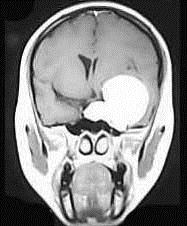

问题 女,36岁,抽搐半年,近10余天头痛加重,磁共振检查如图,选择最可能的诊断()

选项 A.胶质瘤 B.脑膜瘤 C.动静脉畸形 D.海绵状血管瘤 E.蛛网膜囊肿

答案 B